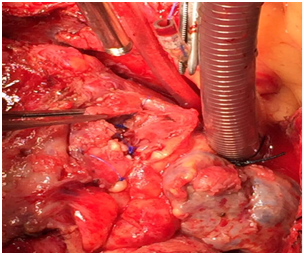

Surgical intervention was done with cardiopulmonary bypass. After Sternotomy, severe dense pericardial adhesion had been seen around the pseudoaneurysdm , adhesion was very carefully dissected, pseudoaneurysm was opened, palpated the stent on RCA, stent had been removed, endarterectomy was done in RCA distal to pseudoaneurysm, 2 small perforation in RCA was repaired by 6-0 polypropylene, RCA proximally and distally ligated with 4-0 polypropylene. Most of the wall of the Pseudoaneurysm had been removed and marsupialization was done. Venous graft was given to distal RCA after long endarterectomy (Figures 1–7).

Figure 6 Ligation of proximal and distal coronary artery.

Figure 7 Venous grafts from aorta to distal RCA after in Pseudoaneurysm endarterectomy.